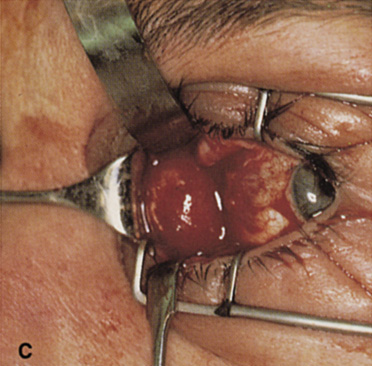

wall still can be carried out. | Fig. 9. A,B. Coronal and axial CT images of a large intraconal neoplasm. C. Because it was felt to represent a well-encapsulated cavernous hemangioma, this

lesion was a candidate for removal via an eyelid crease orbitotomy

without bone removal. The eyelid crease incision marked. D. Incision made with scalpel. E. Orbicularis muscle is tented up and incised to expose the underlying septum. F. Dissection of a skin-muscle flap deep to orbicularis exposes the orbital

septum and superior orbital bony rim. G. Cutting cautery is used to incise periosteum along the superior and lateral

rims; finger palpation of the bone helps to direct this incision. H. Periorbita is elevated along the mesial surface of the lateral orbital

rim in order to expose the deep orbital tissues. I. The cavernous hemangioma is visualized in the wound. Retraction is provided

by one or more malleable retractors. J. Cryoprobe is affixed to the hemangioma to facilitate manipulation of the

lesion. K. Large cavernous hemangioma after removal through the eyelid crease incision

which was accomplished without bone removal. L. Periorbita is reattached over the lateral rim. M. The eyelid crease incision is closed with a running suture. |